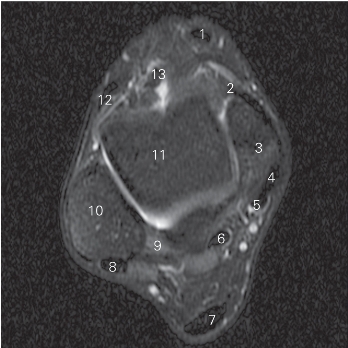

图5-37 经踝关节下方的横断层MR T2WI FS

1 胫骨前肌 tibialis anterior 2 关节囊 joint capsule

3 距骨 talus 4 胫骨后肌 tibialis posterior

5 趾长屈肌 flexor digitorum longus 6

长屈肌 flexor hallucis longus

7 跟腱 tendo calcaneus

8 腓骨长、短肌 peroneus longus and brevis

9 外踝 lateral malleolus

10 距腓后韧带 posterior talofibular ligament

11 距腓前韧带 anterior talofibular ligament

12 趾长伸肌 extensor digitorum longus